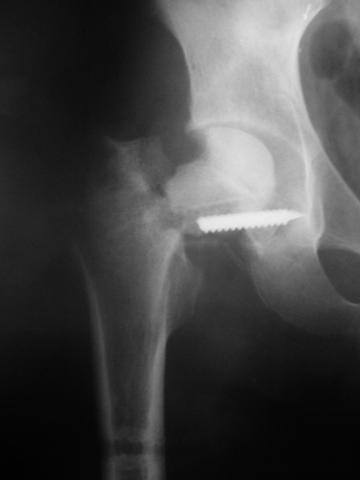

Уважаемые коллеги!молодой человек 22 лет обратился к нам с жалобами на умеренную боль в в/3 левого бедра и паху при ходьбе, укорочение левой ноги. 3 года назад получил закрытый перелом шейки левого бедра (рис 1).

Лечился в стержневом аппарате по месту жительства. АВФ демонтировали через полгода из-за воспаления в области стержней (рис 2). После демонтажа в течение месяца больной лихорадил до 38*, были боли в бедре. Эти явления исчезли после курса антибиотиков. Через год после травмы в ЦРБ ему имплантировали биполярный протез (рис 3). Рана зажила первично. Ходил с костылями, слегка приступая на ногу. На контрольных осмотрах выявлена прогрессирующая протрузия (рис 4-6).